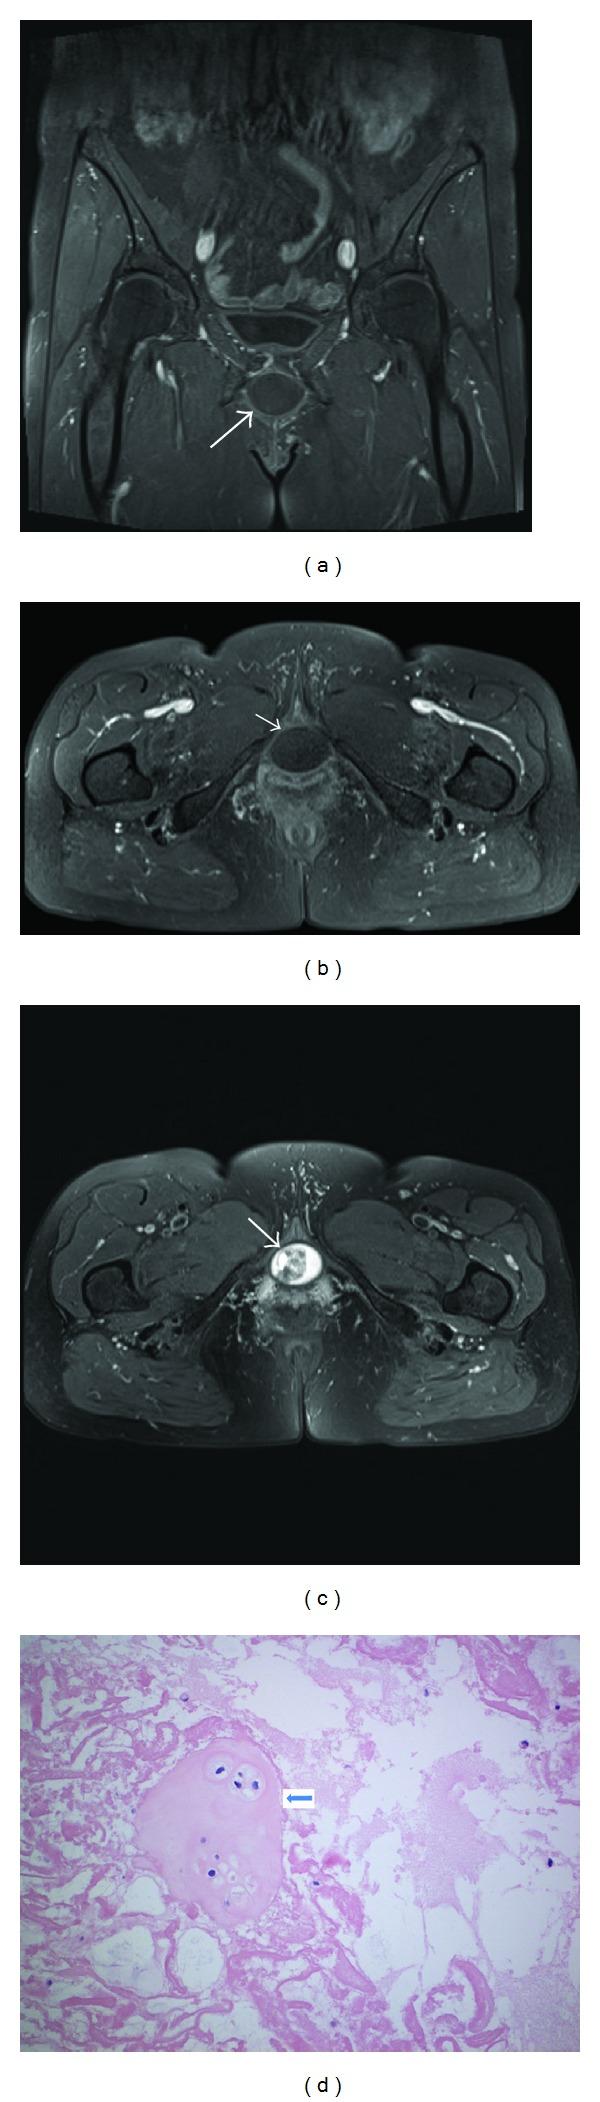

Introduction. Masses arising from structures adjacent to the female urethra can cause obstructive urinary symptoms. Subpubic cartilaginous pseudocyst is a rare degenerative lesion of pubic symphysis that may cause these symptoms. Materials and Methods. A 61-year- and 57-year-old women presented with symptoms of difficult micturition and dyspareunia. Physical examination revealed a painless smooth, rounded, firm, and cystic mass, at the anterior vaginal wall of about 4 cm width. The mass caused inward deviation of the external urethral meatus. Cystoscopy and MRI were done. Results. Cystoscopy of case 1 (61 y) demonstrated anterior external urethral compression with normal urethral mucosa. Cystoscopy was not possible in case 2 (57 y) because the urethra could not be entered under local anesthesia. MRI showed almost the same findings in both cases: midline, rounded, and cystic mass ~3 × 3 × 4 cm, anterosuperior to the urethra, and posteroinferior to the pubic symphysis, with normal features of the urinary bladder. Open surgical excision of theses lesions was performed in both patients. Histopathologic assessment of the specimen obtained from both patients showed degenerated hyaline with areas of fibrinous and mucoid degeneration, a picture suggestive of cartilaginous subpubic pseudocyst. After 11-month and 4-month followup of patients numbers 1 and 2, respectively, there is no evidence of local recurrence of the lesion, either clinically or radiologically and both patients void empty. Conclusions. Subpubic cartilaginous pseudocysts are rare benign lesions with only 13 cases were reported in the literature. Patients present with a spectrum of gynecological and/or urological manifestations. Sizable lesions severely compressing the urethra need surgical excision to restore the voiding function.

结果。病例1(61岁)的膀胱镜检查显示尿道外口前方受压,尿道黏膜正常。病例2(57岁)因在局部麻醉下无法进入尿道而未进行膀胱镜检查。MRI在两个病例中显示几乎相同的结果:中线处、圆形、囊性肿物,大小约为3×3×4厘米,位于尿道前上方、耻骨联合后下方,膀胱形态正常。两名患者均接受了这些病变的开放性手术切除。对两名患者获取的标本进行组织病理学评估显示,有透明质退变区域伴有纤维蛋白样和黏液样变性,这一表现提示耻骨下软骨假性囊肿。分别对患者1和患者2进行11个月和4个月的随访后,临床及影像学检查均未发现病变局部复发的证据,且两名患者均能排空尿液。